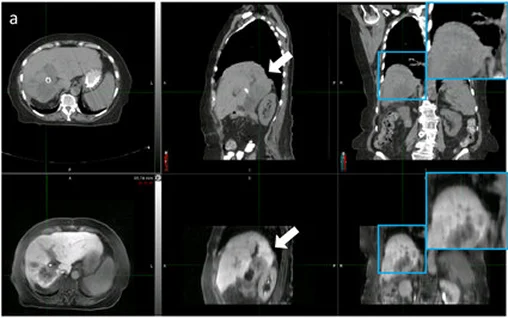

Medical image segmentation refers to the process of partitioning an image into meaningful regions, such as identifying organs, tumors, or lesions. This step is crucial because it enables AI models to focus on relevant structures, improving disease detection and treatment planning.

Creating 3D models from medical images adds a spatial dimension critical for diagnostics, surgical planning, and simulation.